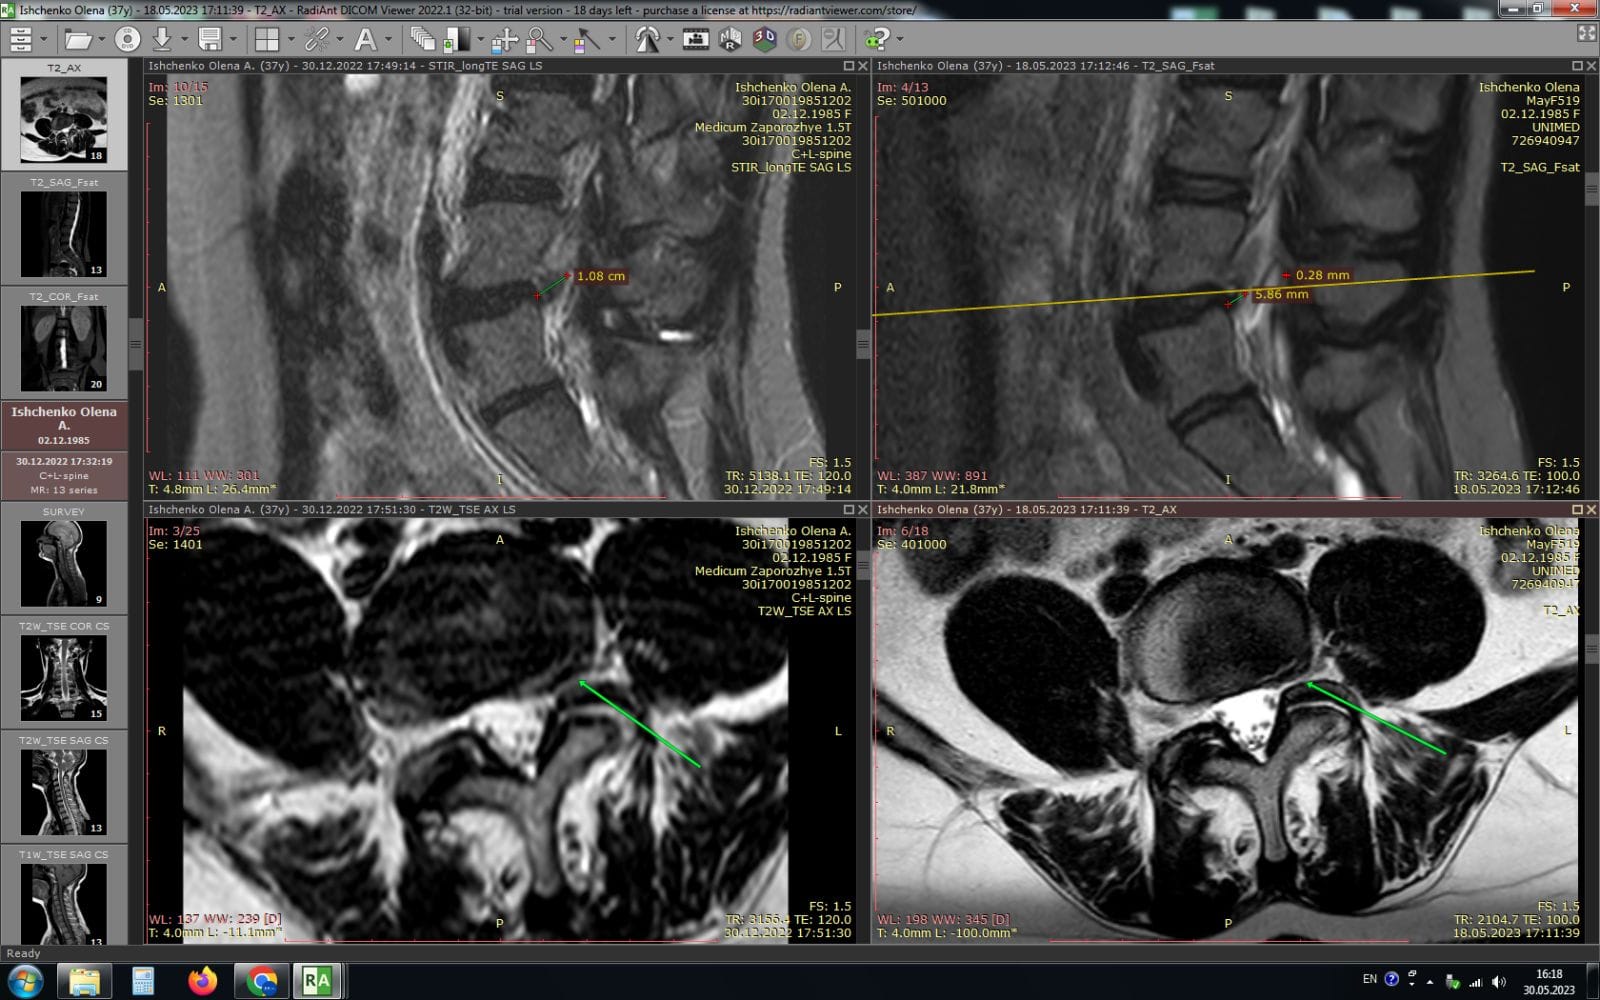

Метод лікування грижі шляхом стимуляції резорбції в Україні був впроваджений у 2020-2021 роках.  Алгоритм оцінки грижі на предмет резорбції, що використовується у клініках – є авторським, розроблений лікарем Боханом А.Ю.